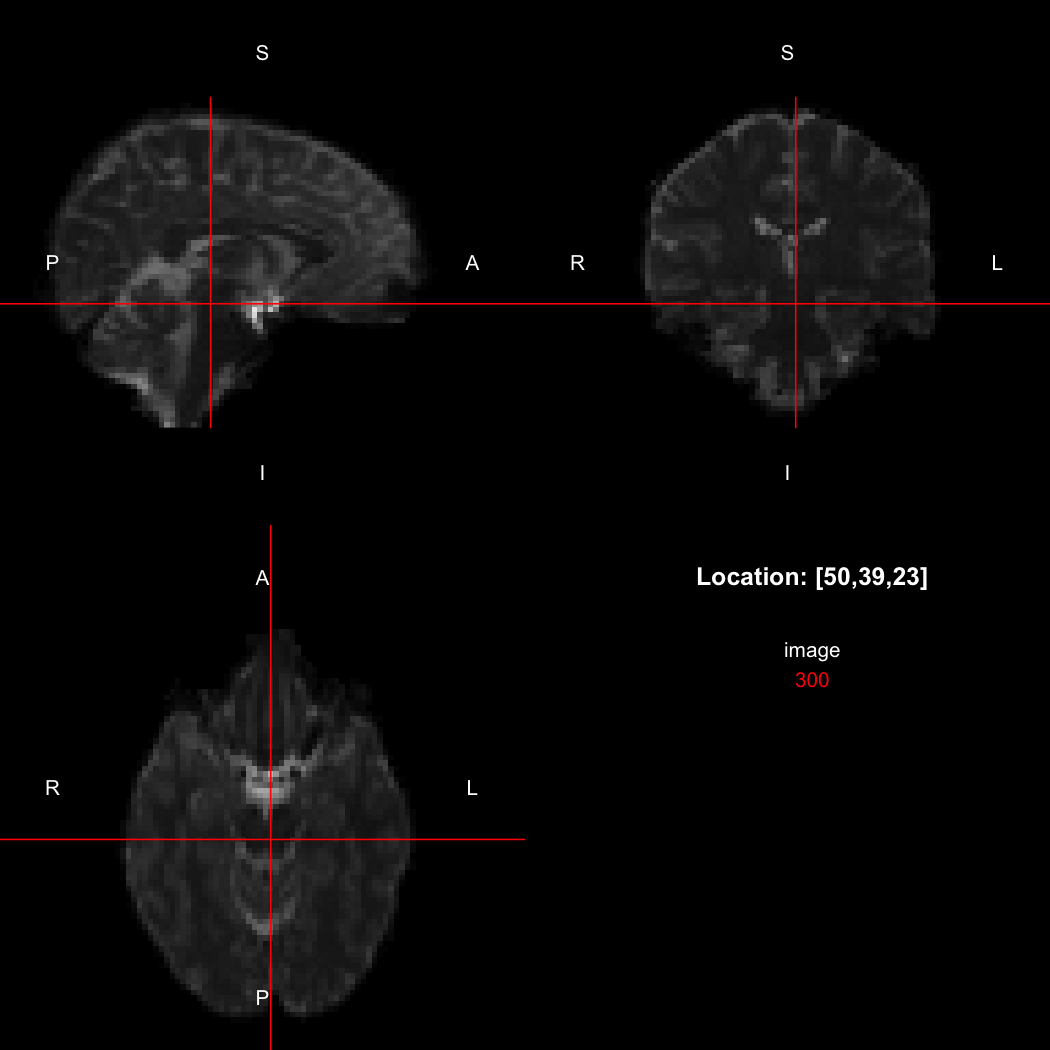

So, here, “LAS” means that the positive x-axis points left, the positive y-axis anterior and the positive z-axis superior. This is the so-called “radiological” orientation convention, and can be requested when viewing images for those who are used to it:

view(image, radiological=TRUE)

plot of chunk unnamed-chunk-12

Notice the left (L) and right (R) labels, relative to the view shown above. Setting the radiologicalView option to TRUE will make this the default for all future views.

orientation(image) <- "RAS"

xform(image)

##      [,1] [,2] [,3]       [,4]

## [1,]  2.5  0.0  0.0 -115.46610

## [2,]  0.0  2.5  0.0  -95.18523

## [3,]  0.0  0.0  2.5  -55.03814

## [4,]  0.0  0.0  0.0    1.00000

## attr(,"imagedim")

## [1] 96 96 60

## attr(,"code")

## [1] 2

image[50,39,23]

## [1] 310

image[47,39,23]

## [1] 300

Notice that the sign of the top-left element of the xform has now flipped, and the value of the image at location (50,39,23) has changed because the data has been reordered. The equivalent x-location is now 47, which is the 50th element counting in the other direction (96 - 50 + 1 = 47).